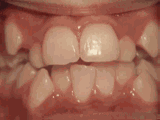

1、牙列拥挤:间隙不足的错颌畸形必须通过拔牙获得足够的空隙,使牙齿和骨量平衡,肌力和牙弓平衡,使矫治效果稳定。

https://pic.wenwo.com/fimg/3555846855.jpg